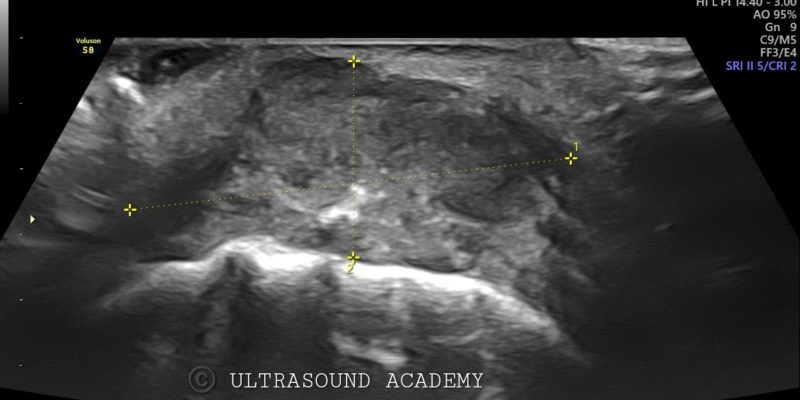

• Hypoechoic irregular mass measuring approximately Approx 1.5 cm in greatest dimension located in the left buccal mucosa.

• The mass shows heterogeneous echotexture with poorly defined borders, invading into the adjacent soft tissues.

• Also an ulcer with air foci seen as hyperechoic specks.